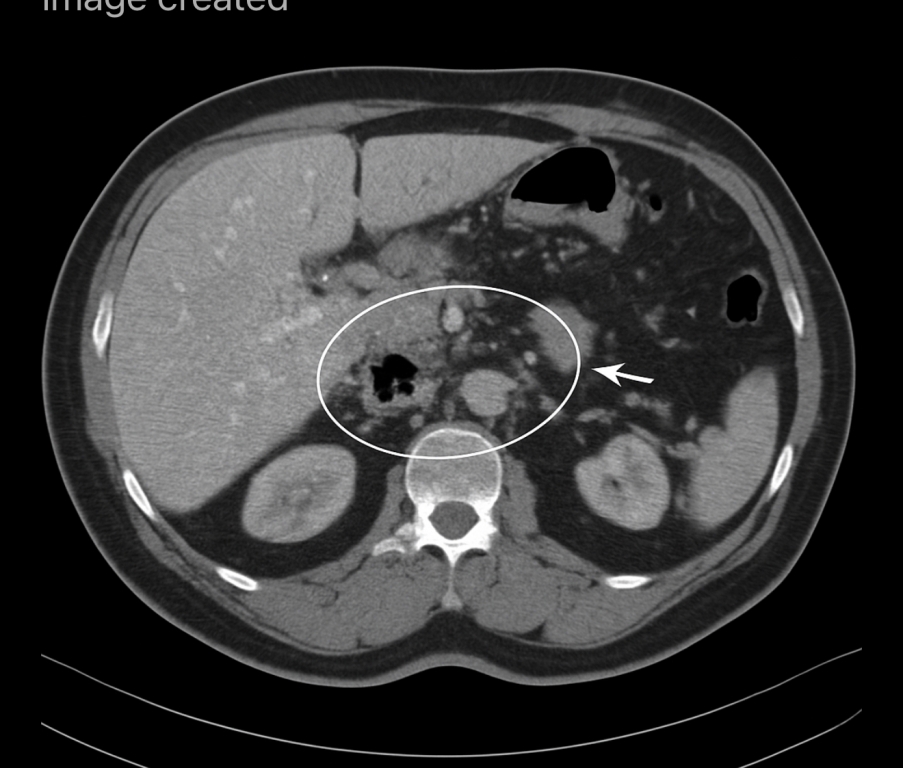

35 year old man with epigastric pain

HOW WILL YOU MANAGE THIS CASE OF ACUTE PANCREATITIS?